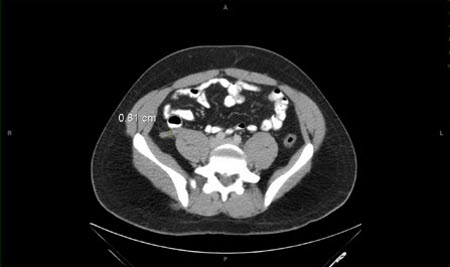

Apendicite: tomografia computadorizada (TC) abdominal mostrando apêndice com espessamento

Cortesia de Nasim Ahmed, MBBS, FACS